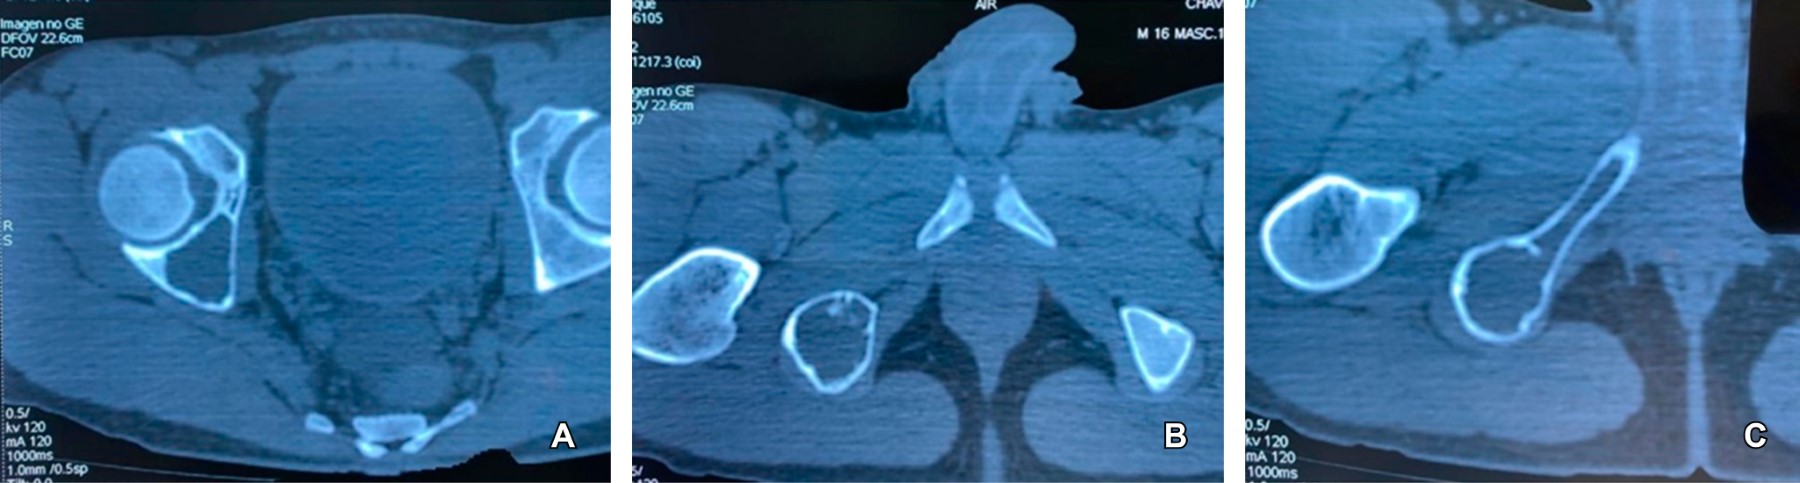

Figure 2